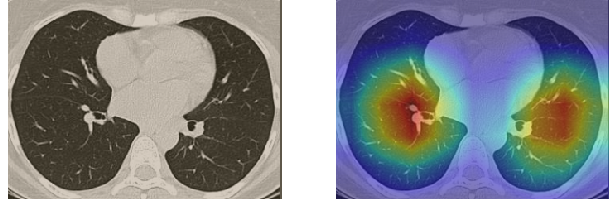

In order to make our models more transparent and provide detailed visual analysis, we present the Grad-CAM localization maps obtained by different models. We consider CT images with COVID-19 abnormalities from the test set of each dataset and highlight the important regions considered for the prediction. For the SARS-CoV-2 dataset we use the Inception V3 model. Figure 13 shows the original CT images and their localization maps. Our model is capable to detect regions that show abnormalities in the CT scans.

In a similar way, we consider classifying the test CT scans from the COVID-19 dataset by the DenseNet169 model and highlight the important regions considered for predictions. We present the original CT images and their localization maps in Figure 13. We can also see that our model is capable to detect the COVID-19 related regions as marked (small square in some images) by expert radiologists.

A wide variety of typical and atypical CT abnormalities have been reported for COVID-19 patients in various studies [58, 59]. So, we tested our models on external CT images extracted from these two publications as they feature typical findings of COVID-19 pneumonia marked by specialists. In order to make sure that not any of the extracted images are unintentionally included in our datasets, specifically the COVID19-CT dataset, we use the model trained on the SARS-CoV-2 dataset. First, the InceptionV3 model is employed to classify the extracted CT images. The model is able to correctly classify the given CT images as COVID-19. Second, in order to interpret the model’s generalization capabilities, we apply the Grad-CAM technique to visualize the regions of abnormalities that are considered. By assessing the different CT images in Figure 15, we can see that the model accurately localizes the disease-related regions. Even more interesting is the fact that the model ignores any specific marks in the images like letters and only localizes the COVID-19 related regions. These visual explanations show the success of our models to learn relevant, generic visual features related to COVID-19 and are capable to correctly classify CT images outside the datasets on which they are trained.